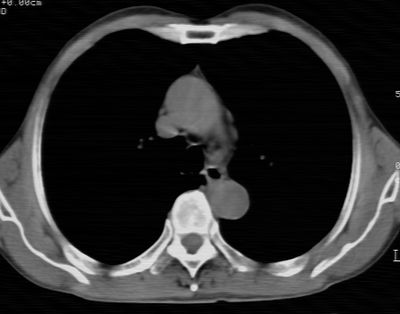

标题: CT24783:m71,既往肺心病史3年,现咳嗽,憋喘。 [打印本页]

标题: CT24783:m71,既往肺心病史3年,现咳嗽,憋喘。

1、左肺上叶spn,毛刺+分叶+血管集束征,考虑周围型肺癌可能性大

1)左肺上叶周围型肺癌可能。2)两肺全小叶型肺气肿。

左上周围型肺癌,全小叶型肺气肿。